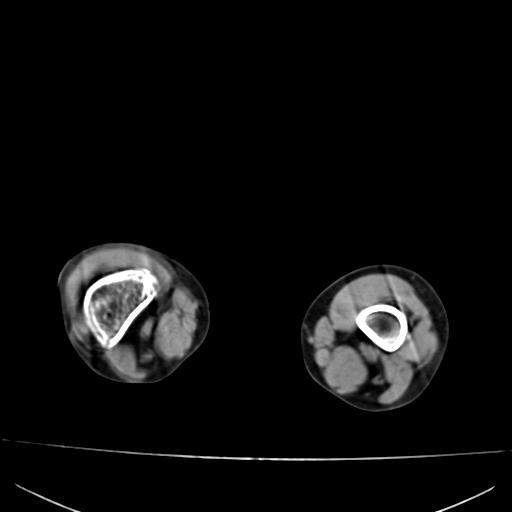

标题: PED0940:M12Y,左股骨下端酸痛畸形 [打印本页]

标题: PED0940:M12Y,左股骨下端酸痛畸形

12岁男孩,左膝关节肿痛8年,近月明显

内生骨软骨瘤?

血友性关节病?